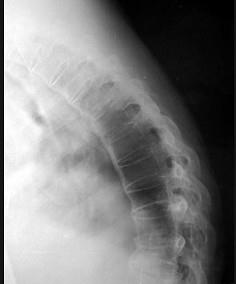

男,48岁,背痛,四肢强直,请结合影像图像,选择最可能的诊断 ( )A、骨脓肿B、骨软骨瘤C、压缩性骨折D、骨囊肿E、强直性脊柱炎

问题 男,48岁,背痛,四肢强直,请结合影像图像,选择最可能的诊断 ( )

选项 A、骨脓肿 B、骨软骨瘤 C、压缩性骨折 D、骨囊肿 E、强直性脊柱炎

答案 E